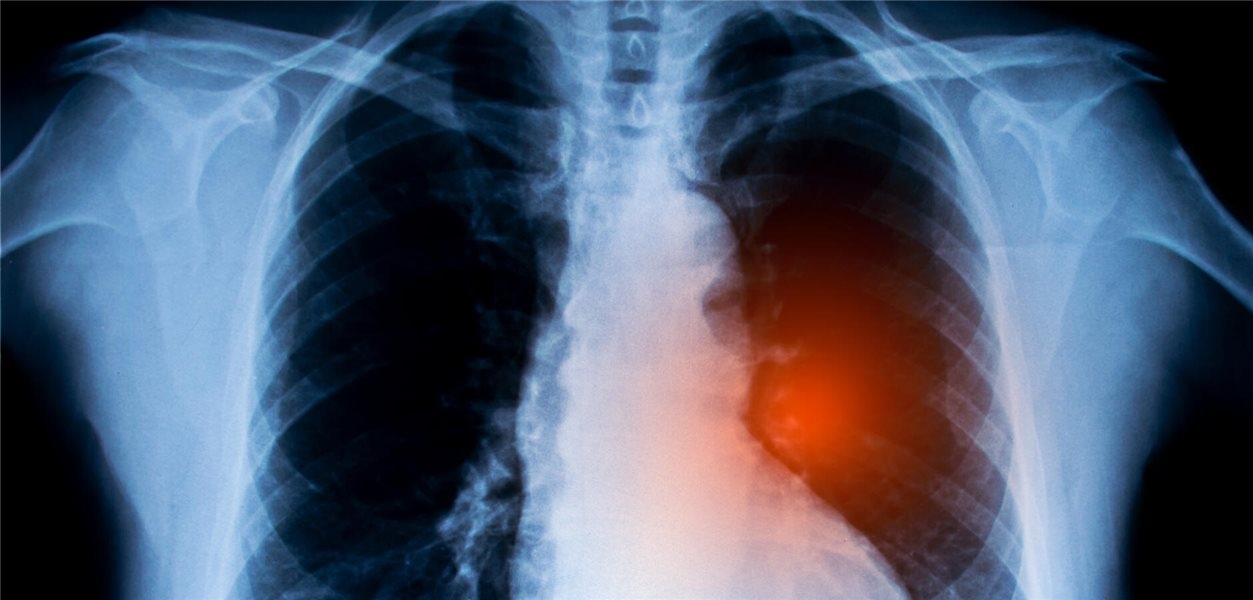

Carcinoma polmonare non a piccole cellule: i vaccini contro il cancro potrebbero aumentare i tassi di sopravvivenza

Per i pazienti con carcinoma polmonare non a piccole cellule in stadio avanzato, i vaccini antitumorali possono essere presi in considerazione anche dopo la terapia di prima linea. Una meta-analisi ne ha esaminato l'efficacia clinica. Un gruppo di pazienti in particolare sembra averne tratto beneficio.